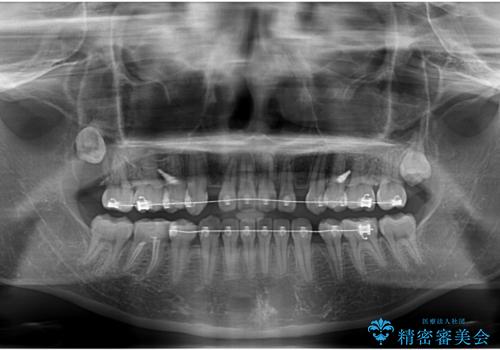

転勤でも安心して治療継続 抜歯スペース閉鎖と深い噛み合わせ改善のワイヤー矯正

- 転勤により東京へ移られることになり転院先を探されていた患者様です。ワイヤー矯正の途中での急な転勤なうえ、今後2~3年以内に再度転勤になる可能性もあるというご事情でした。

そのため、限られた期間内に効率よく治療を完了するために、「抜歯スペースの確実な閉鎖」「深い噛み合わせ(過蓋咬合)の改善」の2点を主軸とした治療計画を立てました。

結果的に1年半で、再度転勤になる前に治療を終えることができました。